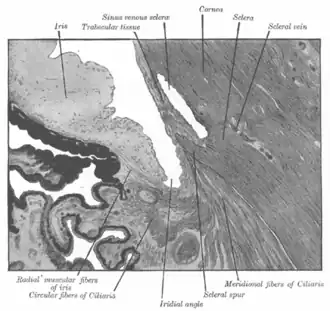

![]() Enlarged general view of the iridial angle. (When enlarged, visible with older label of 'trabecular tissue') | |

The trabecular meshwork is an area of tissue in the eye located around the base of the cornea, near the ciliary body, and is responsible for draining the aqueous humor from the eye via the anterior chamber (the chamber on the front of the eye covered by the cornea).

The meshwork is divided up into three parts, with characteristically different ultrastructures:

- Inner uveal meshwork - Closest to the anterior chamber angle, contains thin cord-like trabeculae, orientated predominantly in a radial fashion, enclosing trabeculae spaces larger than the corneoscleral meshwork.

- Corneoscleral meshwork - Contains a large amount of elastin, arranged as a series of thin, flat, perforated sheets arranged in a laminar pattern; considered the ciliary muscle tendon.[2]

- Juxtacanalicular tissue (also known as the cribriform meshwork) - Lies immediately adjacent to Schlemm's canal, composed of connective tissue ground substance full of glycoaminoglycans and glycoproteins. This thin strip of tissue is covered by a monolayer of endothelial cells.